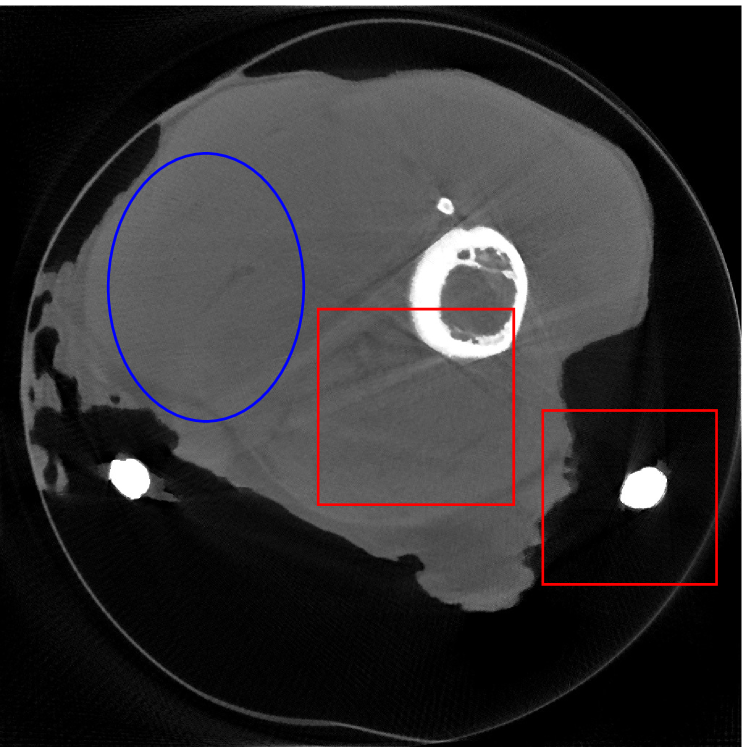

4.2 Numerical experiments: real data

We perform a CT scan of a chicken leg placed in a disposable cup (Figure 10(a)). We first scan the chicken leg without metals (Figure 10(b)) to create a reference image using FBP algorithm. Then, we place two steel thread nails on each side of the chicken leg and scan the subject again using the same scanning protocol (Figure 10(c)). The projection data is acquired from a MicroCT scanner equipped at the Division of Nuclear Technology and Applications, Institute of High Energy Physics, Chinese Academy of Sciences. The X-ray source is with 90 kV and 70 mA energy and the flat plane detector contains pixels. The scanning trajectory is a full circle with equally spaced views at per view. The physical size of each detector unit is . The distance from the X-ray source to the detector is . In order to conduct a 2D experiment, we choose the 512th row of the detector array.

Figure 11 shows the images reconstructed using FBP, the analysis model (2.12), the inpainting model (2.13) and the segmented image from the image obtained by (2.14). The reference image without metal implants are shown in Figure 11(a). All the images in this subsection are displayed within the grayscale interval . The segmented image shown in Figure 11(e) is used to estimate the weights needed in NMAR and the re-weighted JSR model.

Figure 12 shows a comparison between the reconstructed image from NMAR and the unweighted JSR model. Figure 13 shows a comparison between the reconstructed images from TV-FADM and the proposed re-weighted JSR model. Zoom-in views are provided in both Figure 12 and Figure 13 for a better visual assessment. As one can see that the reconstructed images from the unweighted JSR model and TV-FADM are less noisy than NMAR as indicated by the blue ellipse curve, whereas NMAR does a better job in preserving image features and suppressing metal artifacts. However, there are also new artifacts around the metal on the right as shown in Figure 12(d). The proposed re-weighted JSR model has best overall performance in terms of feature preservation, noise and metal artifact reduction.